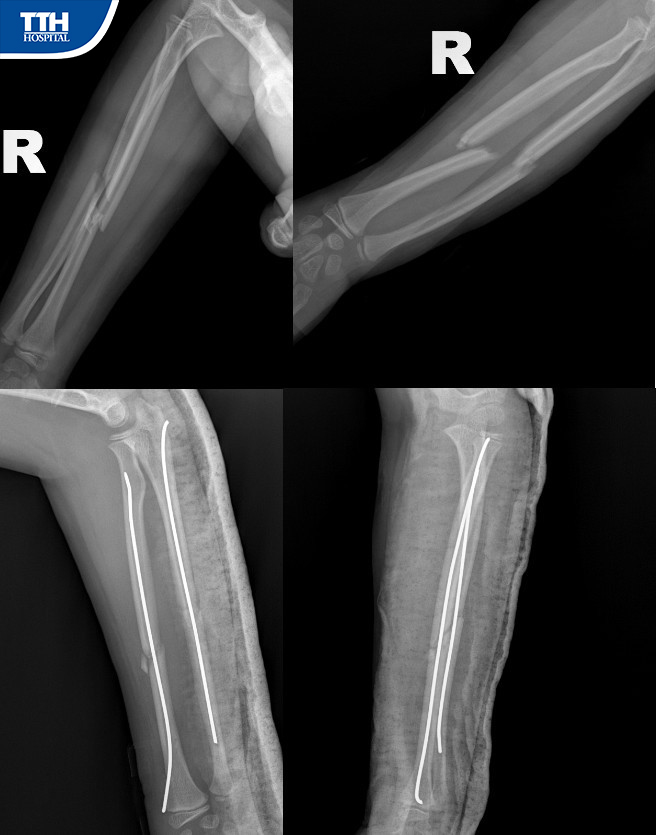

Trường hợp bệnh nhân nhi Đ.L.A.T (11 tuổi, Kỳ Anh) nhập viện theo lời kể của phụ huynh bé cho biết: ''Bé bị ngã trong tư thế chống tay. Sau ngã, tay sưng nề, cẳng tay bị cong, gồ lên do sự di lệch. Gia đình đã đưa bé vào Bệnh viện Đa khoa TTH Hà Tĩnh để thăm khám, điều trị''.

Tại đây, Bé A.T được các Bác sĩ khoa CT-YHTT chẩn đoán gãy kín 1/3 giữa 2 xương cẳng tay phải, cần phẫu thuật kết hợp xương bằng đinh dẻo nội tủy.

Phẫu thuật viên tiến hành nắn chỉnh xương gãy về vị trí giải phẫu qua màn hình tăng sáng. Với đường rạch da tối thiểu 1 cm, cho đinh vào ống tủy để cố định bằng đinh ổ gãy dưới sự hướng dẫn của máy C-arm. Ca mổ diễn ra thuận lợi sau 30 phút thực hiện. Sau phẫu thuật 2 ngày, tay bệnh nhân có thể vận động nhẹ nhàng và được ra viện.

heo Ths. Bs Nguyễn Quang Trưởng khoa CT-YHTT cho biết: “Trước đây, những bệnh nhân gãy xương đều phải mổ mở với đường rạch lớn, bộc lộ mô mềm, màng xương xung quanh để tiếp cận đến ổ gãy, sau đó nắn chỉnh và kết hợp xương bằng đinh hay nẹp vít. Việc ứng dụng kỹ thuật xâm lấn tối thiểu, chúng tôi chỉ cần đường rạch nhỏ trên da, nắn xương và luồn phương tiện cố định xương gãy dưới sự hỗ trợ đắc lực của thiết bị hiện đại: máy C-arm, bàn nắn chỉnh hình cùng các loại nẹp, đinh vít thế hệ mới''.

Với kỹ thuật này, bệnh nhân đau ít, không mất máu, hạn chế nguy cơ nhiễm trùng, phục hồi chức năng sớm. Đây cũng là kỹ thuật khó, thường được thực hiện ở các Bệnh viện chuyên sâu, là xu hướng của kết hợp xương trong điều trị gãy thân xương ở trẻ em.